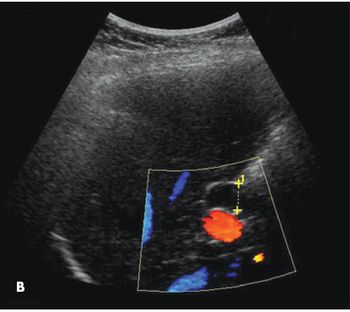

A 60-year-old woman with a 3-month history of progressively worsening epigastric pain was referred for elective cholecystectomy after ultrasonography showed findings consistent with chronic cholecystitis (A and B). The patient reported having postprandial abdominal discomfort since 4 years of age. She also had occasional nausea and vomiting but denied jaundice, change in bowel habits, or urinary symptoms.